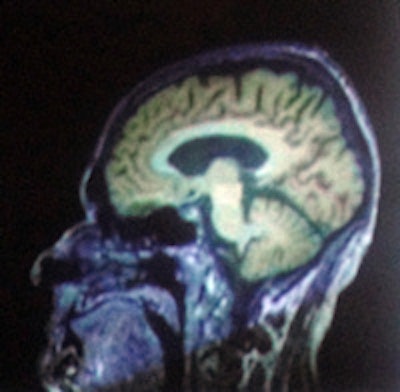

MP-RAGE T1 image of a brain tumor combined with a PET image by F-fluoroethyl-tyrosine (FET). All images are courtesy of N. Jon Shah, PhD.

In a brain tumor imaging study, the use of hybrid scanning with F-fluoroethyl-tyrosene and ultrahigh-field MRI not only depicted the precise delineation of the tumor, it shows how it affects the surrounding brain regions, Shah said.